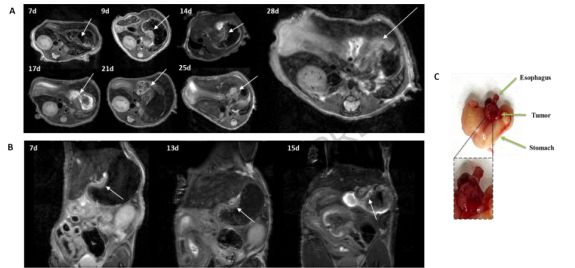

【Scientific Reports】Investigating probe-receptor interactions and enhancing fluorescence guided surgery with fluorescence lifetime imaging and NF-800 in HER-2 positive esophageal adenocarcinoma

荧光寿命成像(FLIM)是研究蛋白质相互作用的利器。本研究将FLIM应用于靶向HER-2的探针NF-800,在食管腺癌动物模型中展示了极高的肿瘤对比度。 这种技术不仅能区分肿瘤边界,还能通过寿命变化揭示细胞生理状态的变化,为荧光引导下的精准癌症手术开辟了新路径。

La Cava, et al., Scientific Reports, DOI: doi:10.1038/s41598-025-31872-8